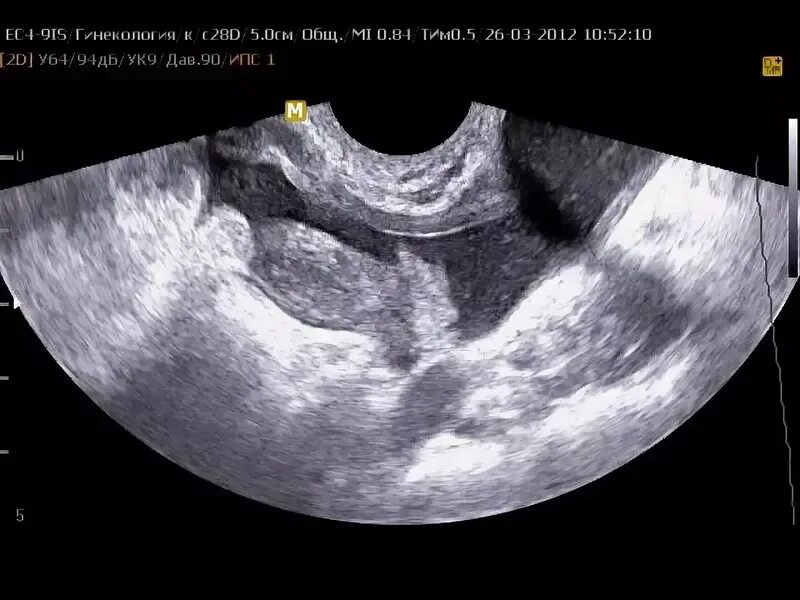

Аднексит диагностика